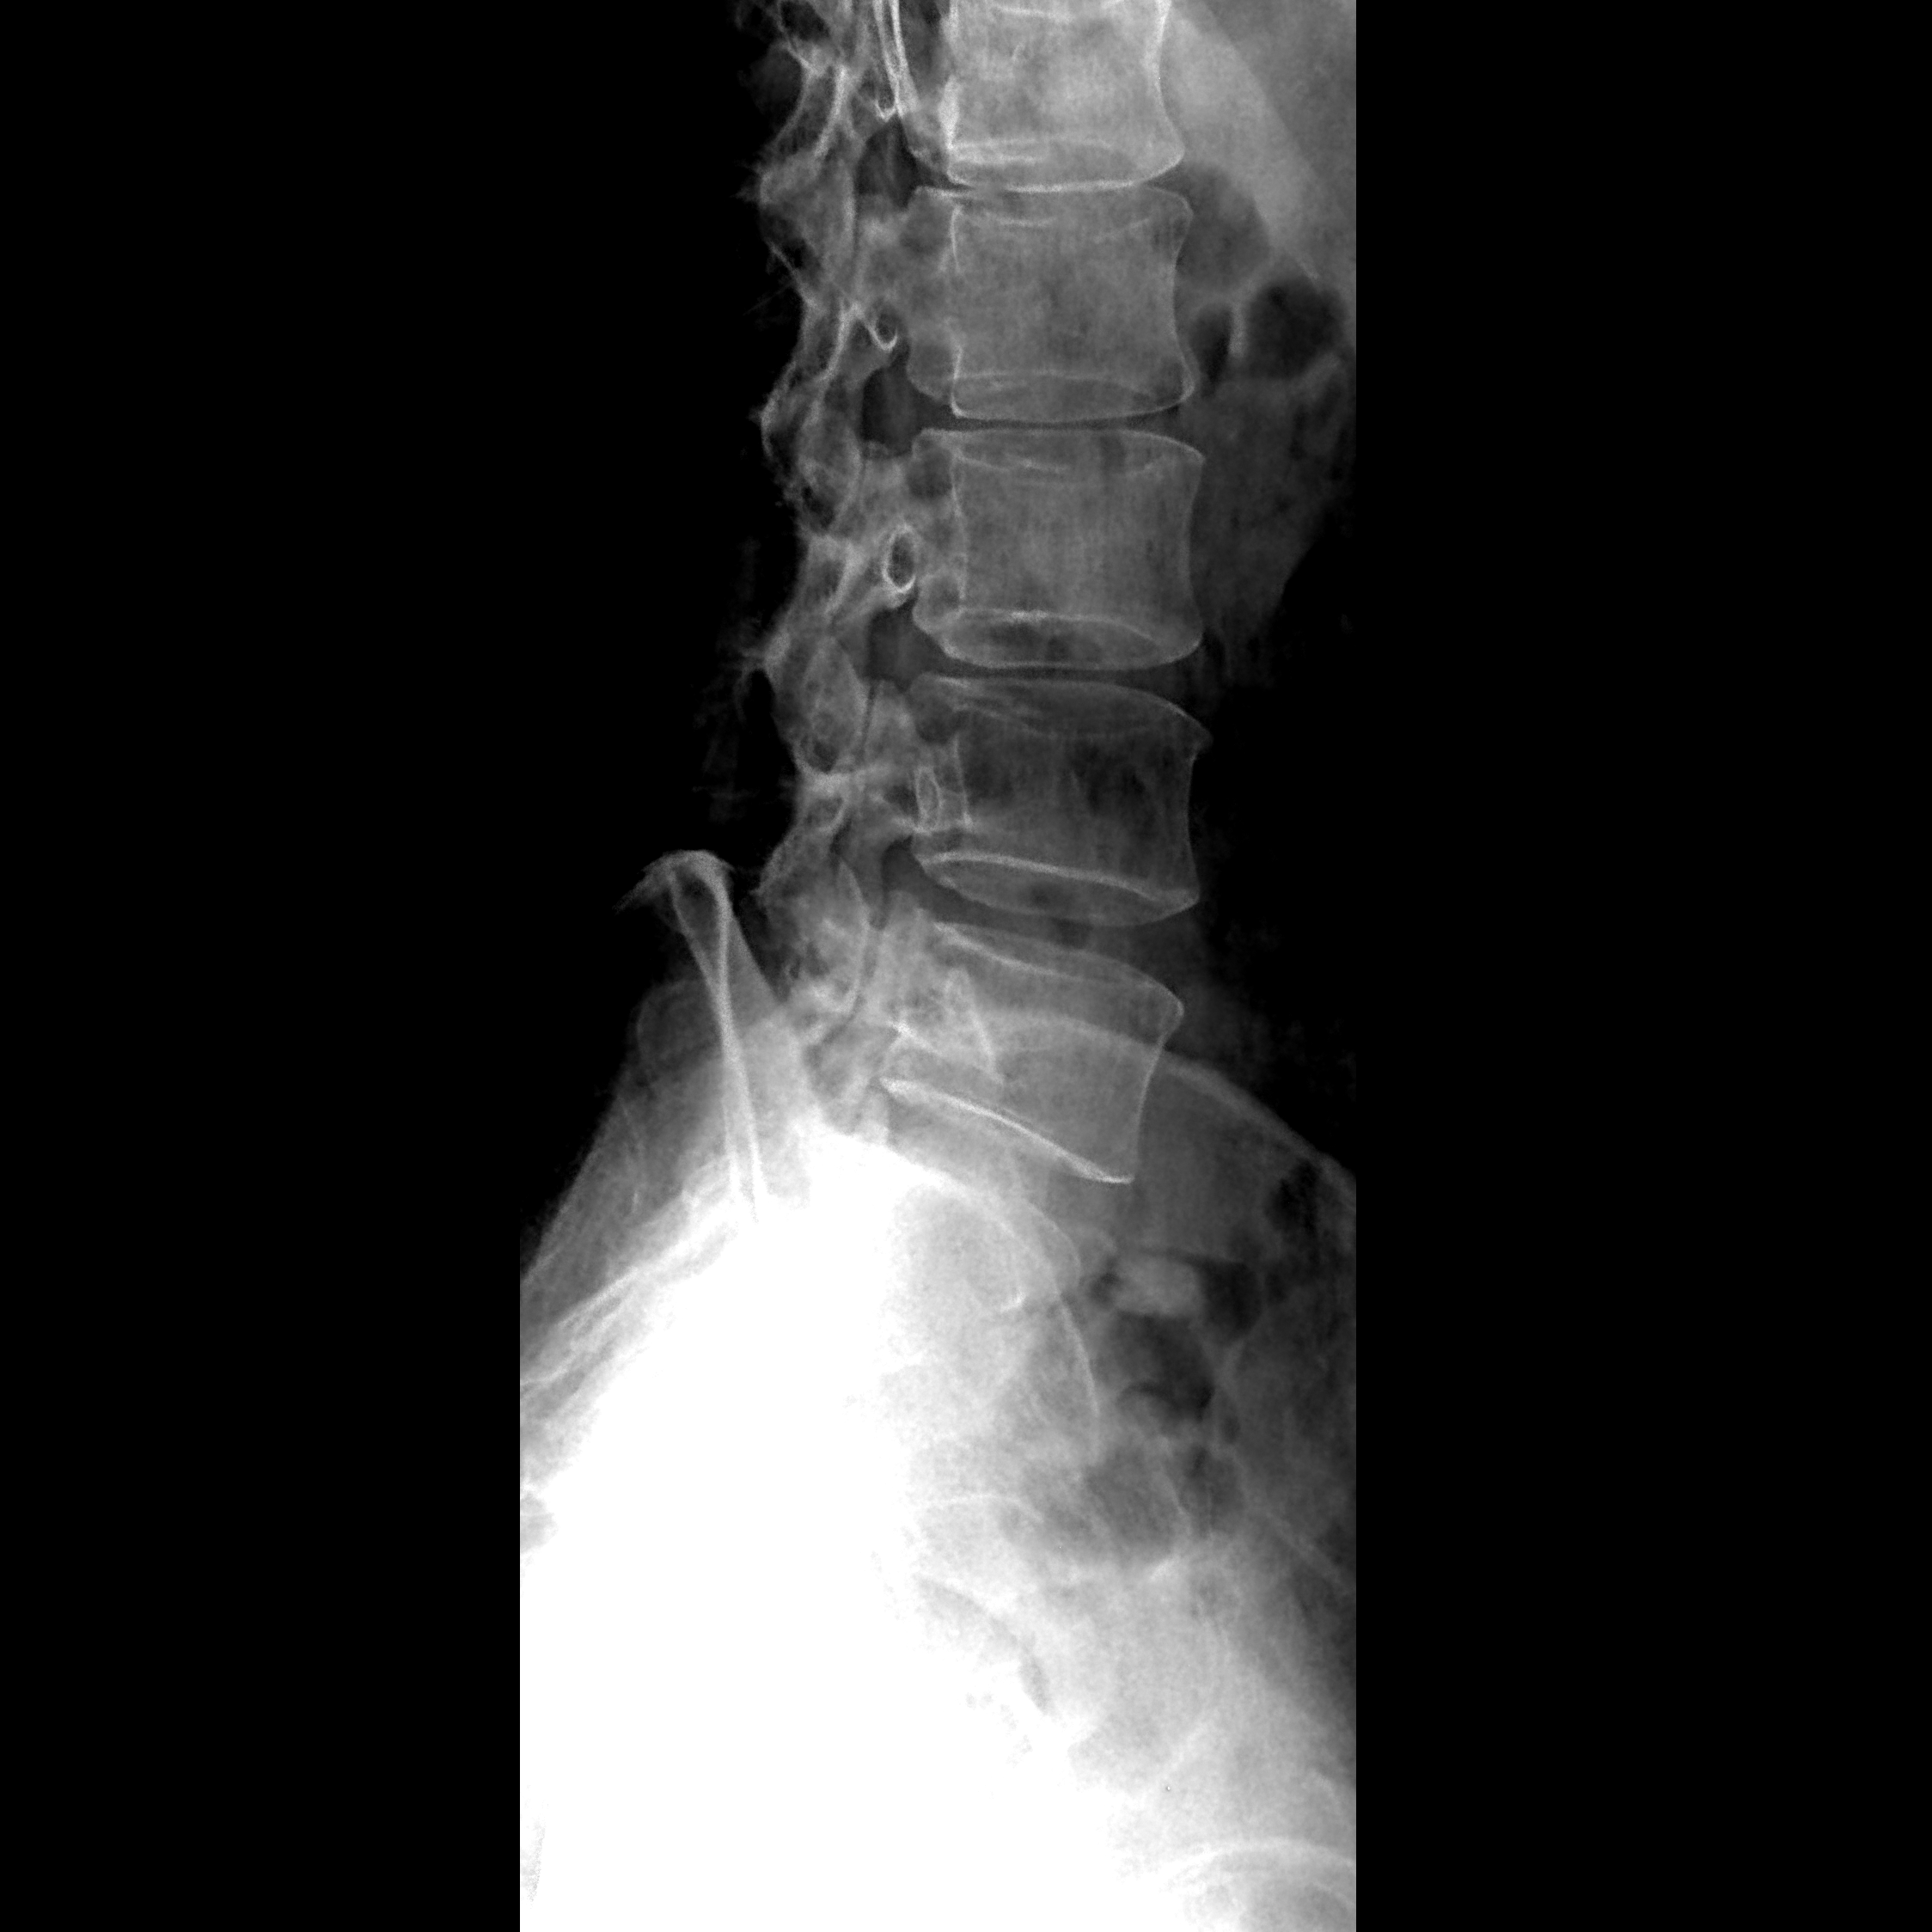

人体骨骼由于含有高原子序数的钙、磷等元素,对X射线的吸收能力较强,因此在X线照片上具有较高的对比度。而肌肉和脂肪等组织则因密度和成分的差异,呈现出不同的对比度。被照体的厚度也会影响X线照片对比度,厚度较大的组织在照片上可能呈现出更深的阴影。